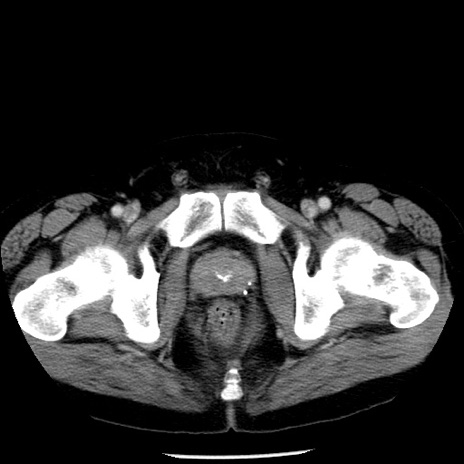

症例29(横断像)

【症例】40歳代男性

【現病歴】2日前から胃痛あり。徐々に周期的な激痛に変化した。本日になっても激痛があるため受診。

【身体所見】意識清明、BT 38-39℃台あり、腹部:膨満、やや硬、右下腹部に圧痛あり。

【データ】WBC 8500、CRP 23.26